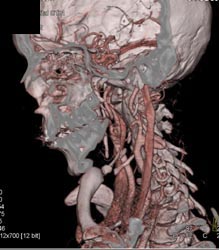

Av Shunt in Liver